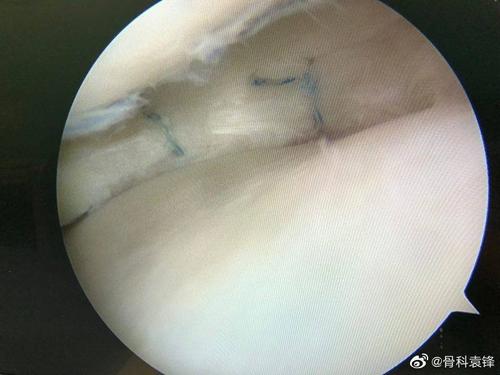

半月板缝合全内allinside技术解读

外侧半月板损伤缝合

半月板撕裂的缝合

全内缝合技术治疗半月板损伤

半月板缝合图片

半月板缝合术